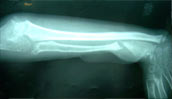

Forearm osteomyelitis